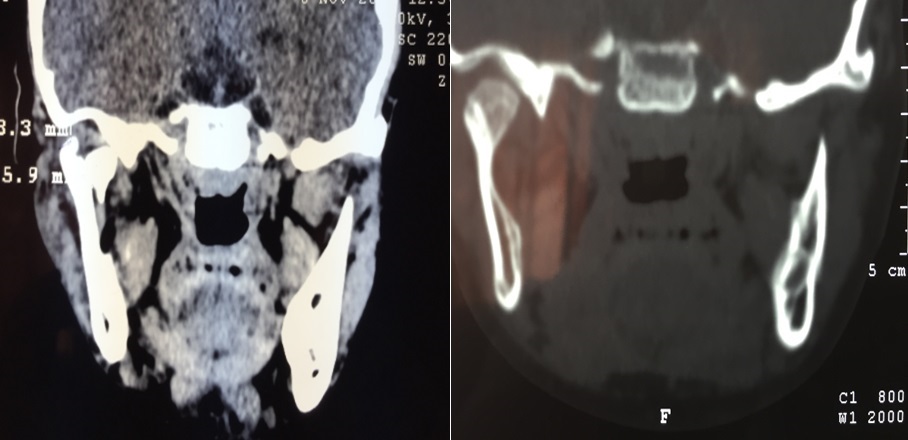

Patients and Methods: A prospective study included thirty patients presenting with condylar fractures, divided into three age groups , group I children less than 12 years old , group II teenagers age range 12-17 years old and group III adult more than 17 years those admitted to maxillofacial department in Al-Basra Teaching Hospital from May,1,2015 until October,30,2016 presented with a malocclusion, a deviated midline, and a limited mouth opening. Computed Tomography is done as early as possible. The method used in our study was the early closed active functional treatment.

Results: Young patients less than 12 years of age were 17 (56.7%), also we found that the dislocation of condylar head fracture was more common in the very young age group according to the CT- Scan. Teenagers patients (12-17) years of age were 2 (6.7%) while adult patients more than 17 years old were 11 (36.7%) .

Conclusion: The complete condylar remodeling (restitution of condylar head) occurs in very young age group (less than 12 years old) and to less extent in others age groups , the diagnosis depend on ct scan findings in pre and post imaging .